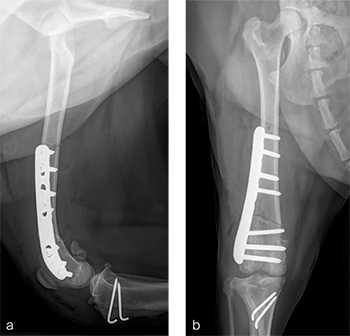

A routine lateral approach to the distal femur and stifle joint was performed. Results of the cruciate ligaments examination were normal. The lateral joint capsule was dissected to expose the distal femoral condyle. An alignment jig was placed in a craniocaudal direction to ensure that deformity correction was limited to the frontal plane. A 12 lateral closing wedge ostectomy was performed and the femoral condyle was reduced and temporarily stabilized with divergent K-wires. A 7-hole left 3.5 LCP DFO plate was placed on the lateral femur and secured with a combination of 3.5 mm cortex and locking screws. The compression function of the plate was used to compress the ends of the two bone segments. Temporary K-wires were removed and a wedge sulcoplasty was performed to deepen the trochlear groove for improved patella articulation. A tibial tuberosity transposition was performed and stabilized with two pins and tension band wire. Routine closure was performed. Total surgical time was 1 hour and 45 minutes. Postoperative x-rays demonstrate the position of a left, 7-hole, 3.5 LCP DFO plate and associated tibial tuberosity transposition. In the medioateral view it can be appreciated that plate contour matches the normal distal femoral procurvatum and screws are positioned caudally away from the trochlea (Fig 6a). This allows for an unimpeded sulcoplasty while maximizing screw purchase caudally. The compression applied with the plate has resulted in excellent apposition. The patella is visible within the trochlear groove. In the craniocaudal view the plate contour matches the anatomical contour of the distal femoral condyle (Fig 6b). The anatomical Lateral Distal Femoral Angle is reduced to 92. During the follow up after 8 weeks, clinical signs have resolved, limb use is excellent, and stifle joint range of motion is normal without evidence of pain. In the mediolateral x-ray the osteotomy has healed (Fig 7a). Plate and screw position remain unchanged. The tibial tuberosity transposition is healing, and implants remain unchanged. The patella remains reduced within the trochlear groove. In the craniocaudal view the osteotomy has healed and is no longer visible (Fig 7b). Implants are stable and the patella is tracking normally.